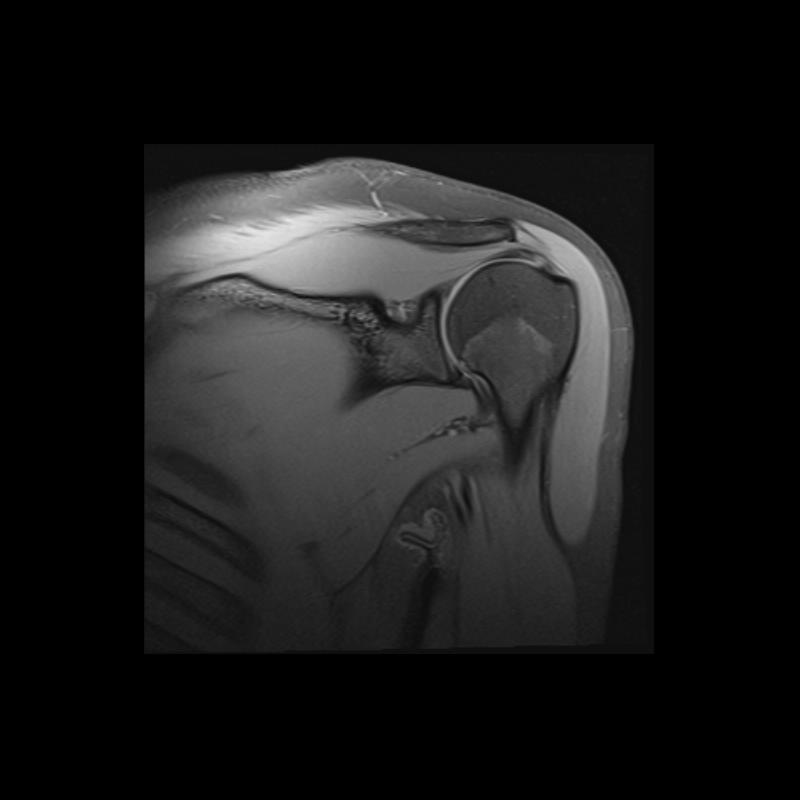

Shoulder MRI Anatomy